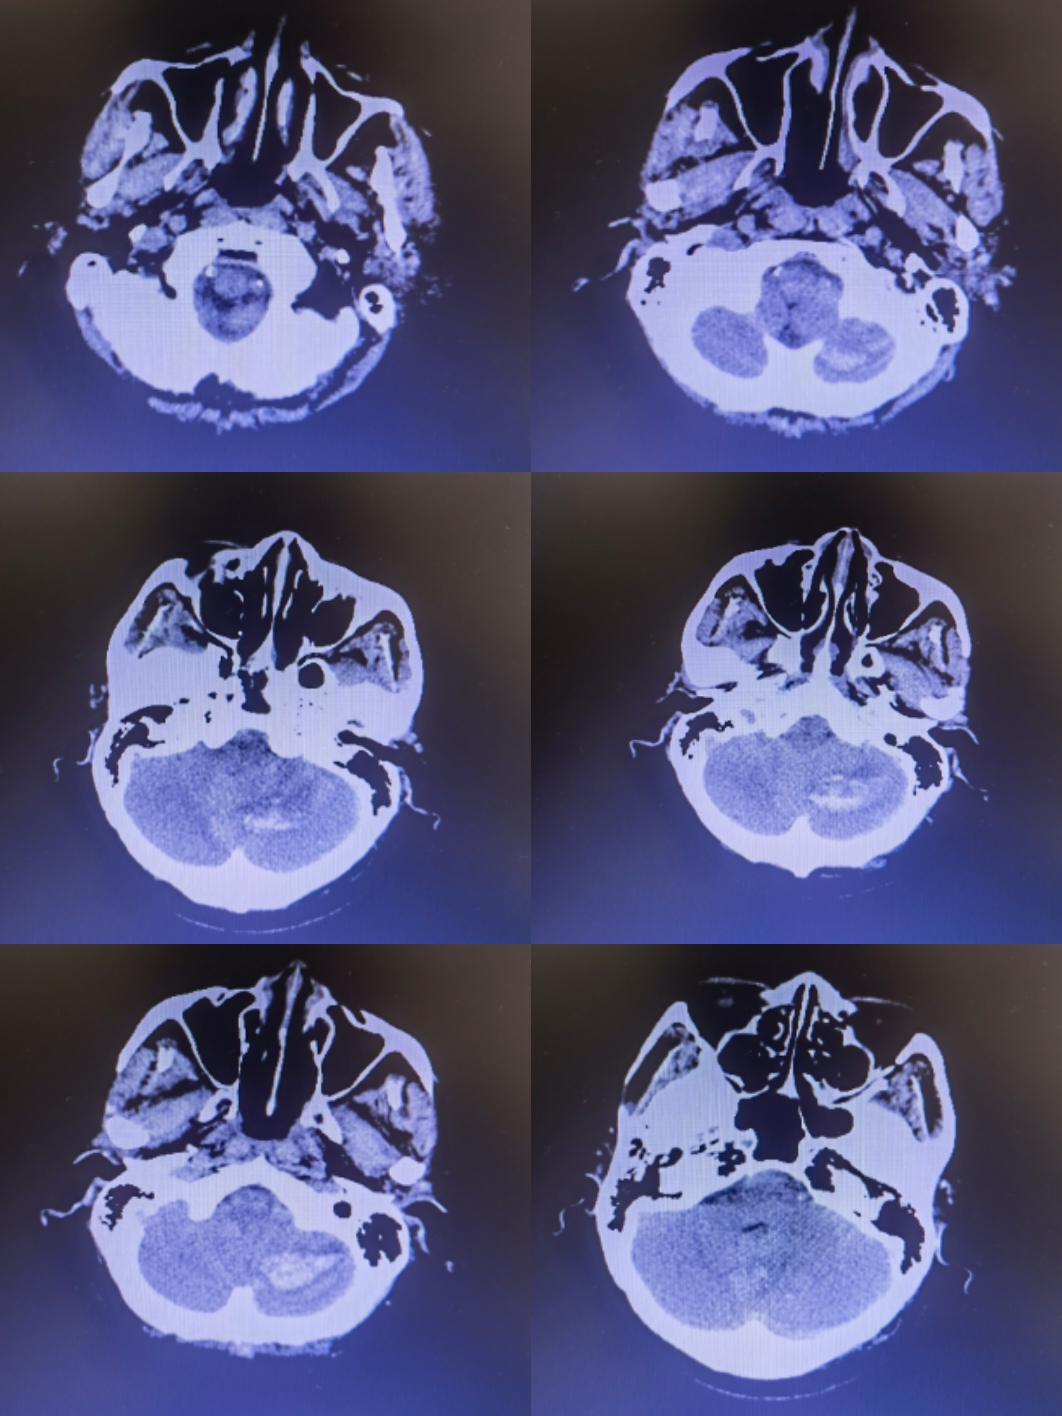

小脑挫裂伤压迫延髓

患者神智嗜睡,给与甘露醇后意识好转,四脑室受压,脑干受压,后期迟发性挫伤和继发性脑肿胀会进一步压迫延髓,给与急诊手术

行脑室外穿刺后行后颅窝去骨瓣减压,术中剪开硬膜后血肿经小脑皮层破出,术后病人意识清楚

思考:小脑挫裂伤后压迫延髓随时可能危及患者生命,早期积极行手术治疗利于患者恢复